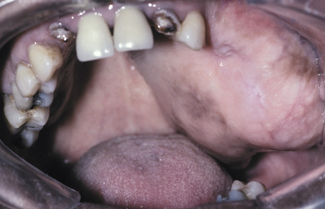

florid cemento-osseous dysplasia